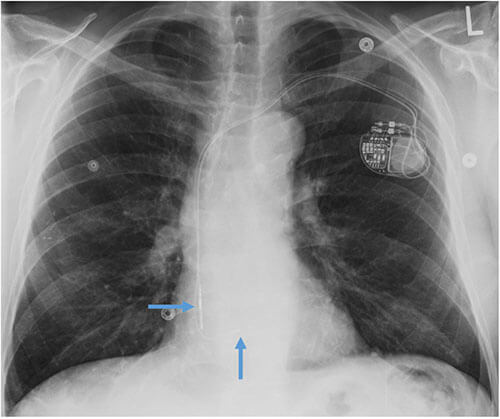

- CEID images with lead types:

Pacemaker with transvenous leads

Pacemaker with epicardial leads

Defibrillator lead

Subcutaneous defibrillator

Cut epicardial wires (often hard to see)

Abandoned leads

Abanded leads plus generator

Temporary transvenous lead

Leadless pacemaker